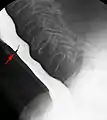

منظر أمامي لتضيق وترة المريء في الباريوم ( فحص ابتلاع الباريوم).